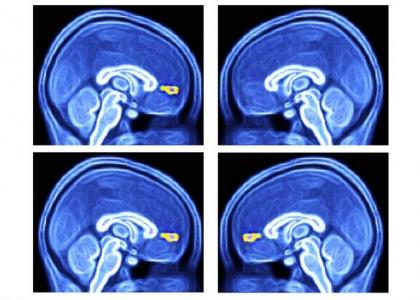

Des scientifiques du Wake Forest Baptist Medical Center (Caroline du Nord) ont mis au point une approche diagnostique simple des troubles du spectre autistique TSA) : l'équipe mesure la réponse d'enfants autistes à différents signaux environnementaux sous imagerie par résonance magnétique fonctionnelle (IRMf). Chez les enfants autistes (visuels du haut) la présentation unique d'objets ou de visages favoris n'active pas une zone spécifique du cerveau, le cortex préfrontal médial ventral. Ce test d’imagerie simple est décrit dans la revue Biological Psychology.

L’équipe a testé la réactivité du cortex préfrontal médial ventral du cerveau (vmPFC : ventral medial prefrontal cortex) aux signaux visuels représentant une interaction sociale « de grande valeur », chez 40 jeunes participants âgés de 6 à 18 ans, dont 12 diagnostiqués avec TSA et 28 suivant un développement normal. Les participants ont passé l’IRMf tout en visualisant 8 images de personnes ou d'objets, chacune plusieurs fois. Chaque série d'images comprenait 2 images choisies de manière individuelle représentant la personne et l’objet préférés de chaque participant. L’expérience montre que la réponse moyenne du vmPFC est significativement plus faible dans le groupe de participants atteints de TSA.

• Le simple recours à des images du patient et à l’IRMf pour capturer 30 secondes de données s’avère donc suffisant pour diagnostiquer l’autisme. « La façon dont le cerveau réagit à ces images est cohérente avec l’hypothèse selon laquelle les cerveaux des enfants autistes ne codent pas la valeur de l'échange social de la même manière que les enfants en développement typique », expliquent les chercheurs.